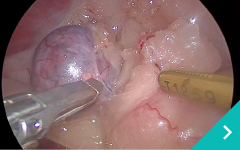

腹腔鏡下

門脈体循環シャント手術

肝臓がん

アブレーション治療

胆嚢肝臓がん摘出手術